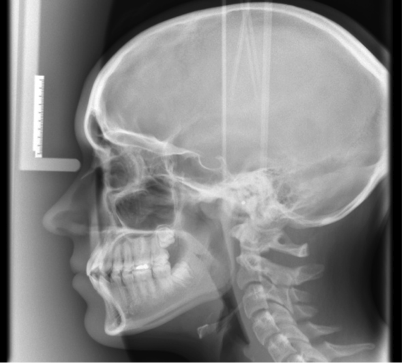

CEPHALOMETRIC RADIOGRAPH

Radiograph of the head, including the mandible in full lateral view, on tracings of these films, anatomic points, planes, and angles are drawn that assist in the evaluation of the patients' facial growth and development.